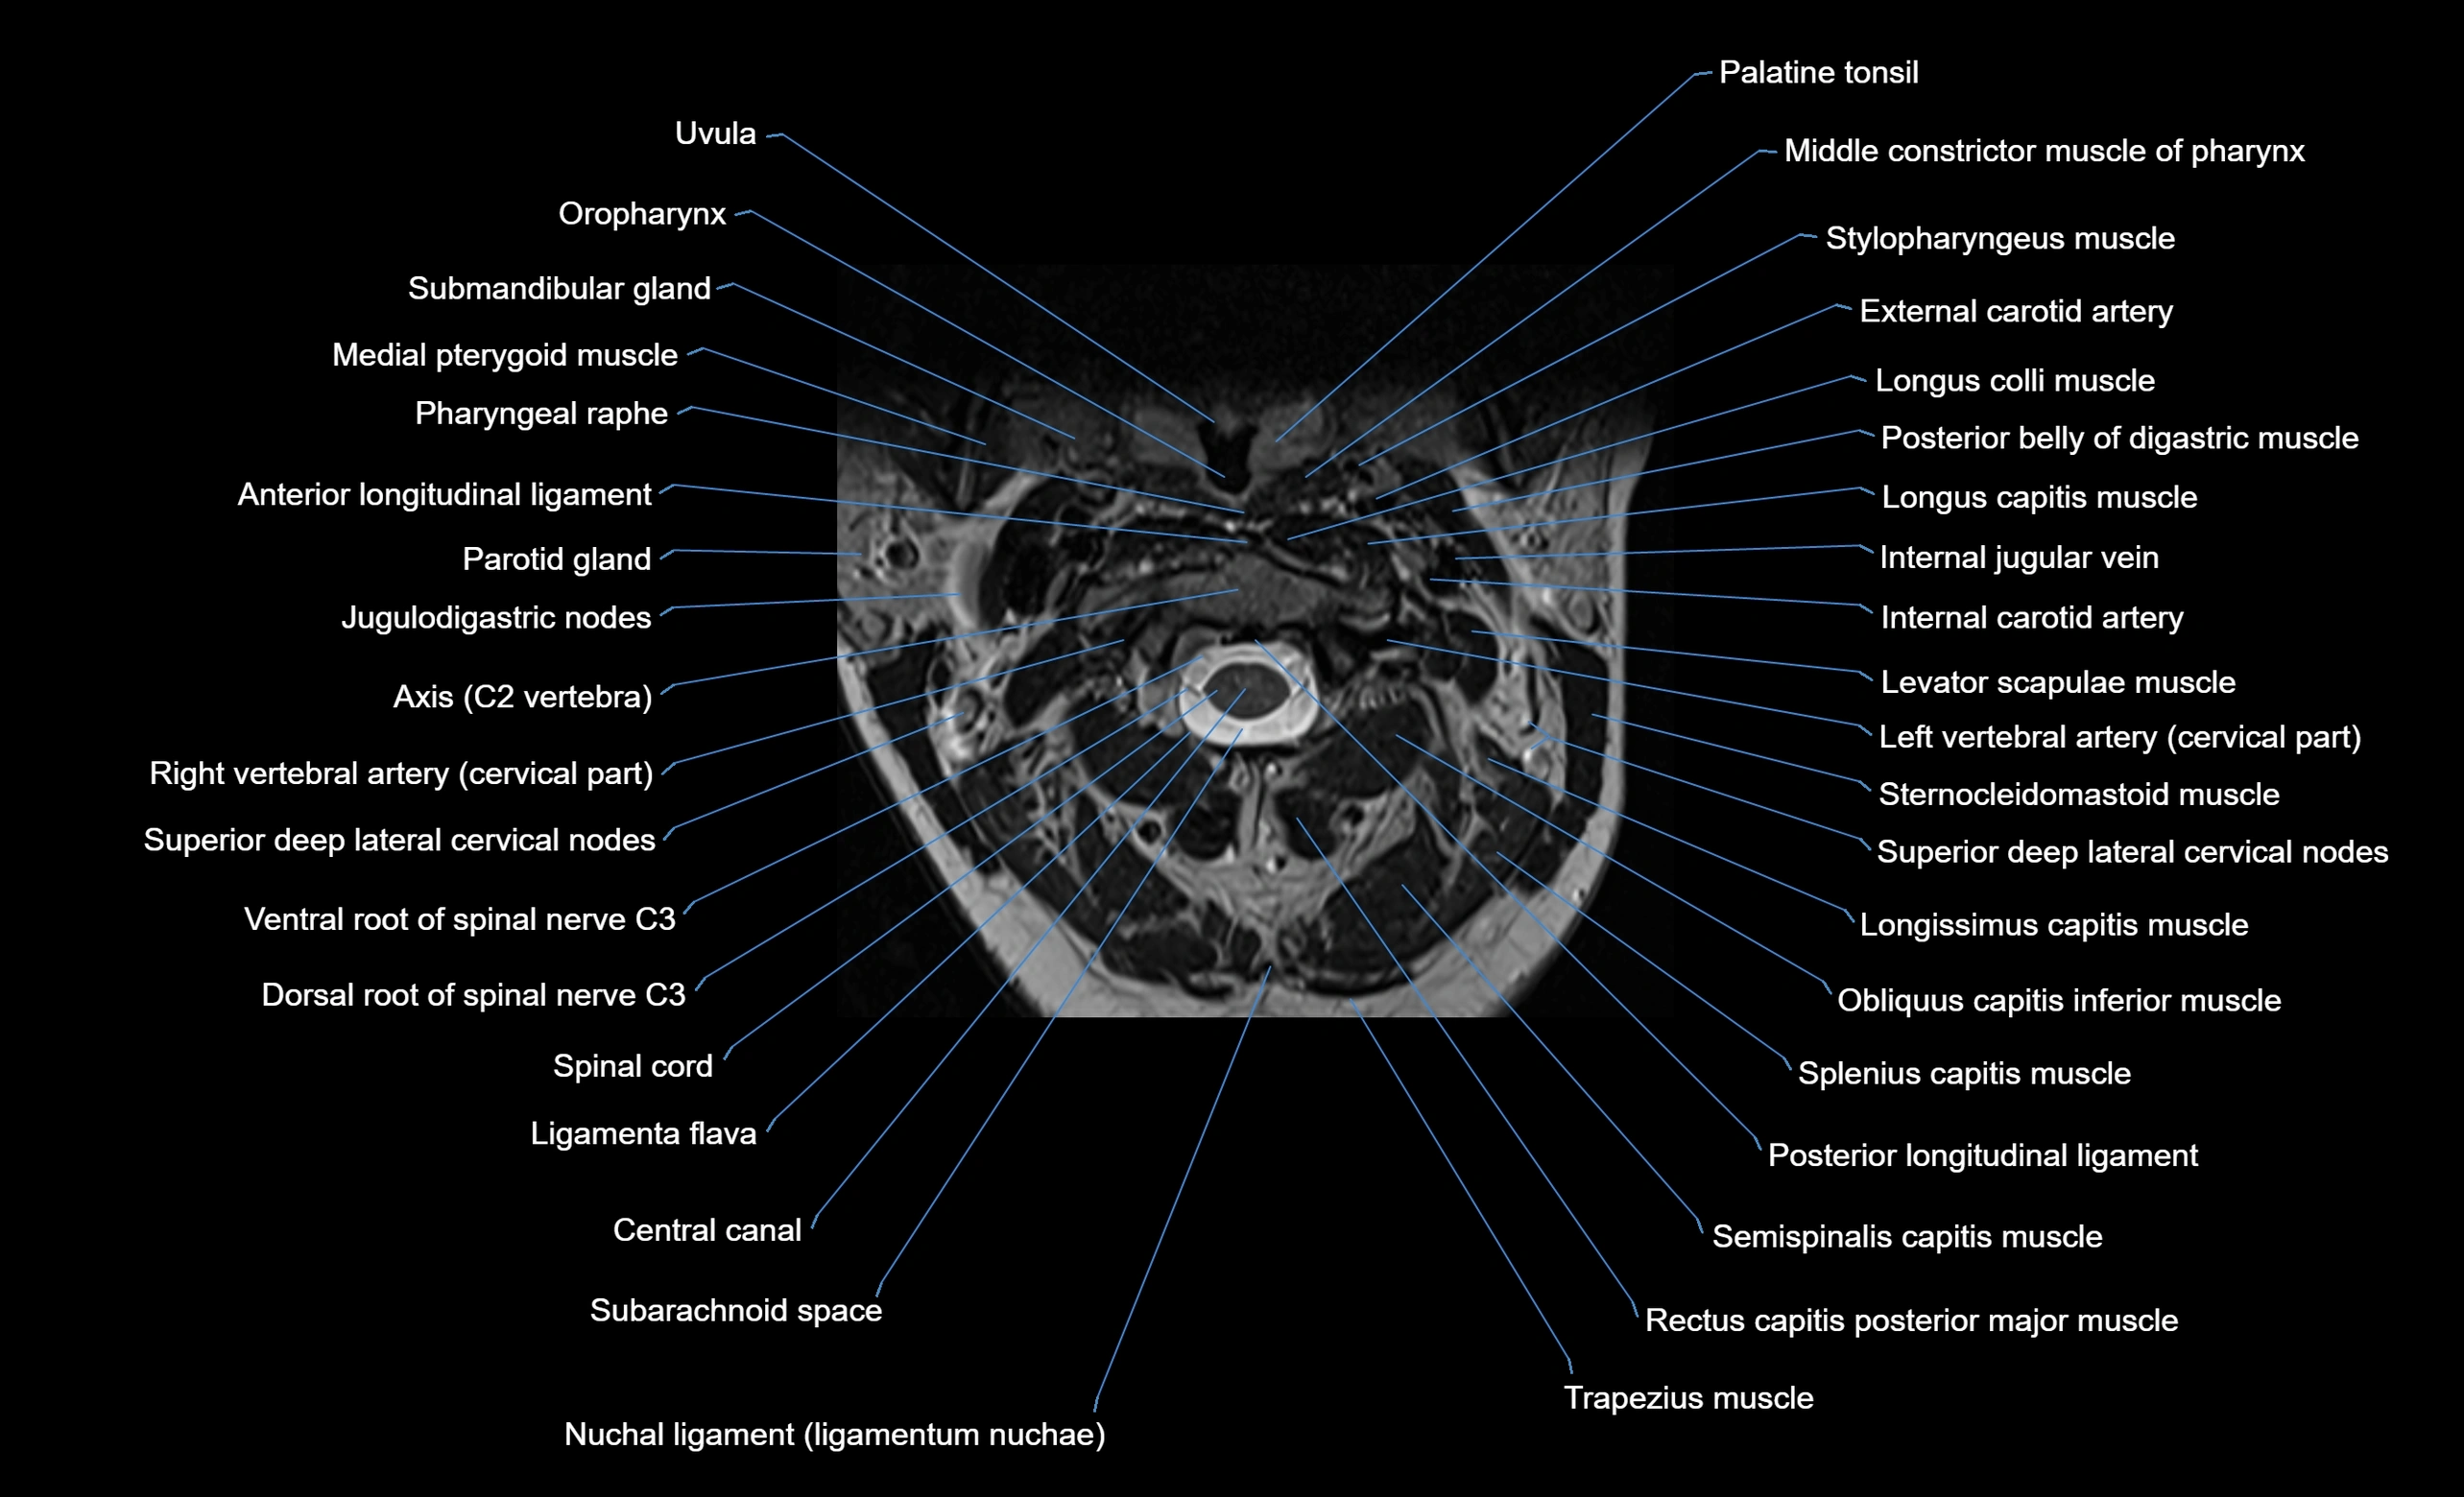

MRI image

image